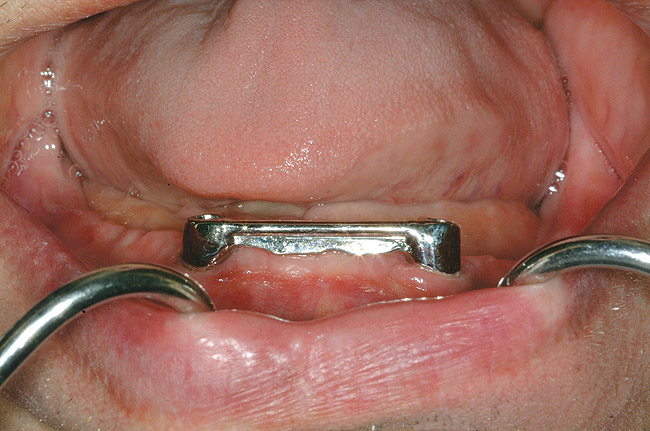

Figure 4  An example of a two-implant tissue bar for an implant-assisted prosthesis.

Figure 4